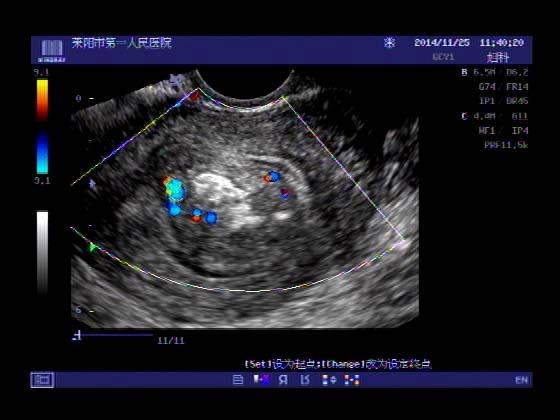

超声入门贴379---------粘膜下肌瘤(阴超的魅力)

女,43岁,月经量多3个多月,加重一个月

外院彩超检查提示:子宫后肌壁略高回声团------肌瘤?息肉?,盆腔少量积液

今天来我院检查:

巧妇难为无米之炊,经腹部超声确实很难定,阴超一目了然,乡镇医院诊断水平的提高更迫切的需要高档仪器的引进!